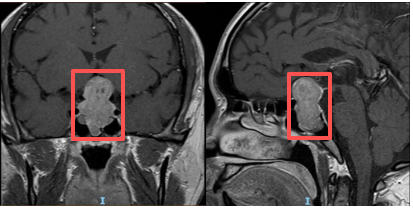

术前垂体增强磁共振可见巨大哑铃型肿瘤

经头颅CT、磁共振等检查,王海军教授团队确诊李先生为“颅内鞍区占位性病变”,通俗来说,就是颅内长了一个压迫神经的肿物。“当时肿物已经对周围脑组织造成了一定压迫,如果再拖延不积极处理的话,可能会出现失明、脑积水甚者昏迷等严重的并发症。”王海军教授回忆道。